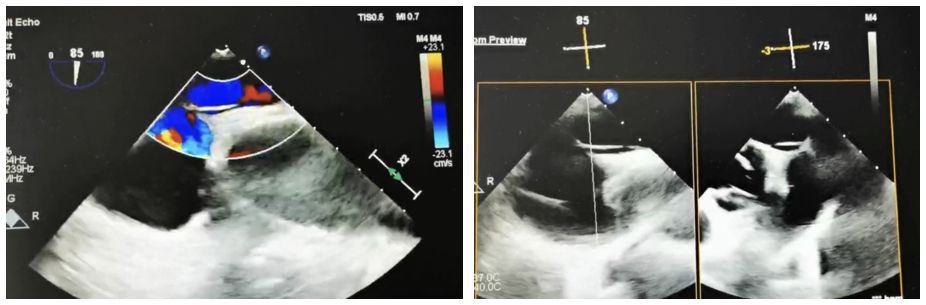

Case Information: A 60-year-old male patient was admitted to the neurology department after experiencing "left-sided limb weakness". The patient underwent a routine transesophageal echocardiogram (TEE), which revealed a patent foramen ovale (PFO) (congenital type, 2.4mm in width, 33mm in length, with moderate shunting). Right heart echocardiography and bubble tests confirmed a grade II shunt.

Estrategia clínica: Se eligió el oclusor simétrico BDPFO-I 2828 para asegurar un cierre óptimo. Durante la fase de liberación, se utilizaron imágenes de DSA para el posicionamiento, mientras que la guía de ultrasonido se empleó principalmente para garantizar un despliegue preciso.

Resumen del caso: Debido a la longitud del túnel, los alambres guía de catéter convencionales y el soporte de la vaina de punción septal no fueron efectivos. Específicamente, se usó un cable guía coronario combinado con una vaina de punción septal en este caso y cruzó con éxito el tabique. Cuando se usan oclusores metálicos tradicionales para cierres de PFO de túnel largo, el material rígido y la posición de cintura fija a menudo evitan que el disco izquierdo se expanda completamente. Esto puede hacer que el disco se tire hacia el túnel, lo que lleva a una deriva residual. En contraste, el oclusor biodegradable, con su fuerte adaptabilidad, permitió que la cintura llenara completamente el túnel y lograra un cierre efectivo.